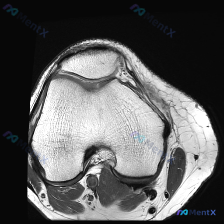

今天碰到一个很典型的「临床-影像矛盾」病例,整理出来和大家一起讨论一下。 病例核心信息 问题:临床高度怀疑膝关节软骨异常,仅提供1张膝关节MRI-T1序列轴位影像(髌股关节层面),要求读片分析。 影像读片结果: 1. 骨性结构:股骨远端、髌骨骨皮质连续,软骨下骨光滑,骨髓脂肪信号均匀,未见异常信号灶...

今天遇到一个有意思的读片问题:只给了一张膝关节轴位MRI,问这里有没有软骨异常,整理一下分析思路分享给大家。 基本病例/影像信息 提供的是膝关节单张轴位MRI扫描图像,可识别的解剖结构包括:前方的髌骨、中部的股骨内外侧髁与髁间窝、髌股关节间隙,以及周围部分软组织。 客观影像所见 1. 软骨结构:髌骨...

看到一份针对单张膝关节MRI的软骨异常评估咨询,整理了完整的分析思路分享给大家。 病例/影像基础信息 问题核心:用户提供单张膝关节轴位T1加权MRI图像,询问图像中是否存在软骨异常。 影像所见(基于提供图像): 1. 扫描层面为膝关节轴位,涵盖股骨远端滑车区与髌骨 2. 股骨髁、髌骨骨髓信号正常(T...

刚遇到一份有意思的膝关节影像病例,整理出来和大家分享一下思路。 病例基本信息 这是一份膝关节MRI T1序列轴位单张图像,核心疑问是评估是否存在「软骨异常」。 影像读片结果 1. 扫描层面是膝关节上部,主要显示髌股关节(髌骨+股骨滑车)和股骨髁 2. 髌骨软骨下骨、股骨髁骨皮质轮廓清晰,骨松质信号均...

病例读片:膝关节软骨异常的影像陷阱 先给大家看一下这份病例的基本影像资料:这是一张膝关节MRI-T1加权序列的轴位图像,扫描层面位于股骨远端髁间窝与髌股关节层面。 影像基本信息整理 1. 骨骼结构:股骨远端骨皮质、骨髓信号正常,髌骨形态完整,骨皮质连续,骨髓信号无异常; 2. 关节软骨:髌骨后方关节...